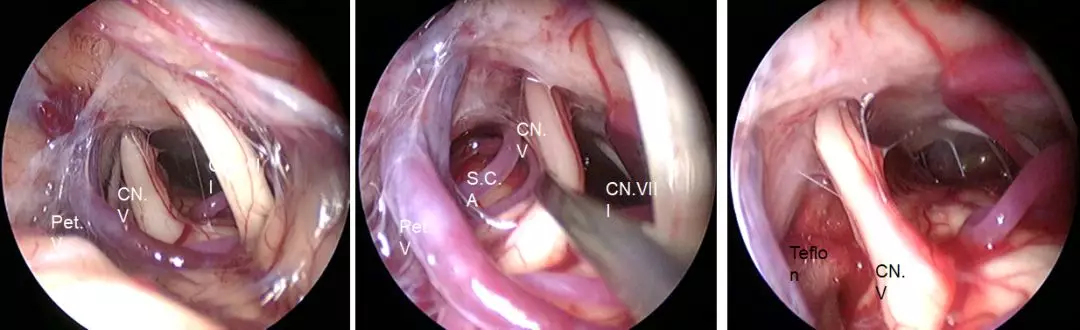

乙状窦后入路的锁孔手术主要应用于一些神经功能性疾病以及下丘脑角肿瘤,可以清晰地看到面庭神经、三叉神经、血管等。采用乙状窦后入路解决三叉神经痛和面肌痉挛时,手术切口又有所不同,三叉神经痛切口稍偏上,而面肌痉挛的切口可以稍偏下一些,这样更容易从神经和血管的间隙达到手术的目的地。

三叉神经减压术要点:

患者采取仰卧位,头侧悬。

在耳后发际内切一个4公分的切口。

铣一个骨窗,或直接用磨钻磨出一个骨窗。

剪开硬膜,暴露脑组织。

进入脑池,放出脑脊液,处理局部病变。